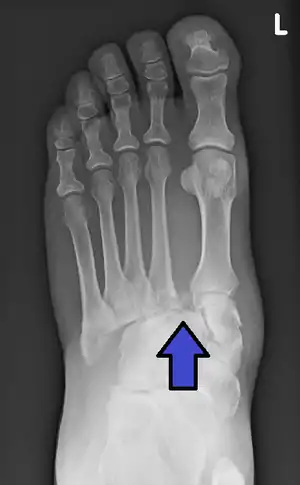

Jones fractureSir Robert Jonesfracture of base of 5th metatarsal extending into intermetatarsal jointinversion of ankleJones fracture Archived 2006-07-02 at the Wayback Machine at Wheeless' Textbook of Orthopaedics online

Lisfranc fractureJacques Lisfranc de St. Martinfracture dislocation of midfootforced plantar flexion of foot or dropping heavy weight on footLisfranc fracture at Who Named It?